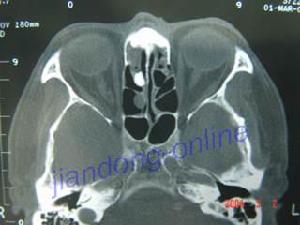

鼻竇軸位平掃鼻竇軸位平掃檢查是通過CT對耳鼻咽喉進行檢查的一種方法。胚胎髮育期組成頜面突的接合處如有上皮組織殘餘存留,以後可漸形成囊腫。其囊壁內襯上皮,外被覆結締組織,囊內含有膽固醇的黃色液體,少數可繼發感染。患者多為女性。其發生於鼻前庭與上頜牙槽突間的骨外,表現為鼻翼、上唇間隆起。CT示在鼻底前區單房低密度囊性腫塊,可致切牙根尖上方的牙槽骨局部骨質壓迫性吸收,鼻梨狀孔下外緣受壓凹陷和擴大。